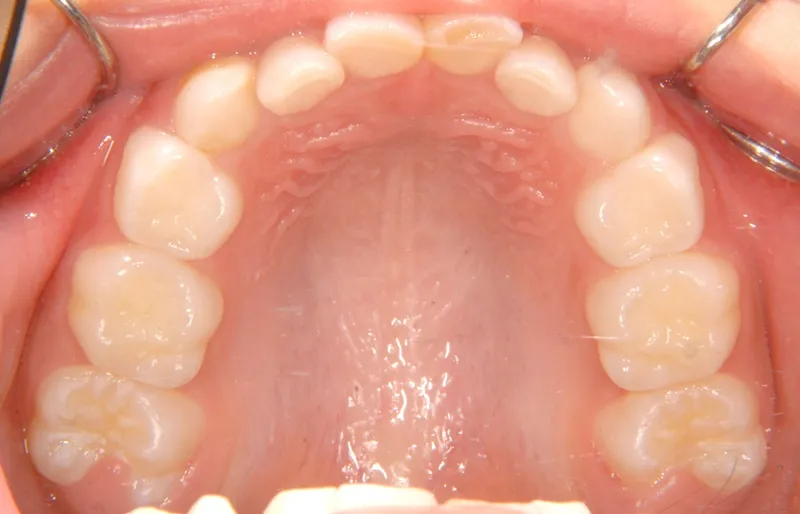

治療終了後

治療回数43回、7年4ヶ月の治療期間で矯正治療を終了しました。

主訴が改善され、ご満足頂きました。